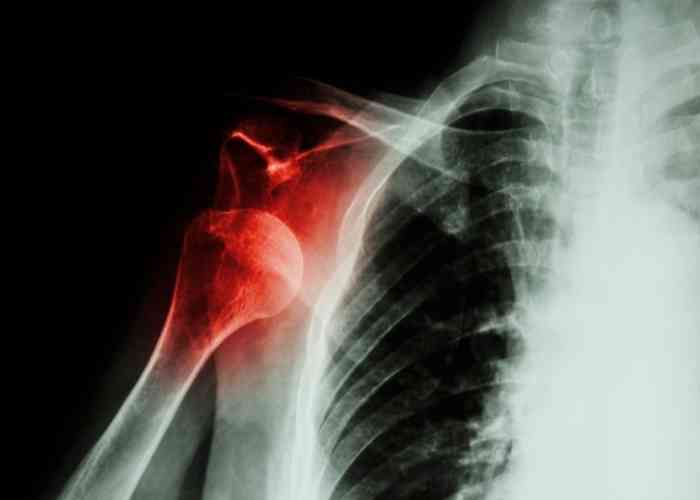

Dorsal Subluxation Shoulder X Ray . Shoulder subluxation is defined as partial or incomplete dislocation of the glenohumeral joint or translation between the humeral head and glenoid fossa while the humeral head is in. In this article we will focus on: This radiograph provides a tangential view of the anterior glenoid and can be quite useful in identifying anterior These labral tears make the shoulder unstable and susceptible to repeated dislocations.